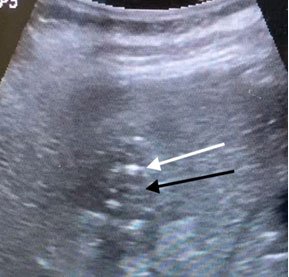

Before procedure liver abcess (arrow)

After procedure (PCD): shrunken liver abcess (black arrow) and drain (white arrow)